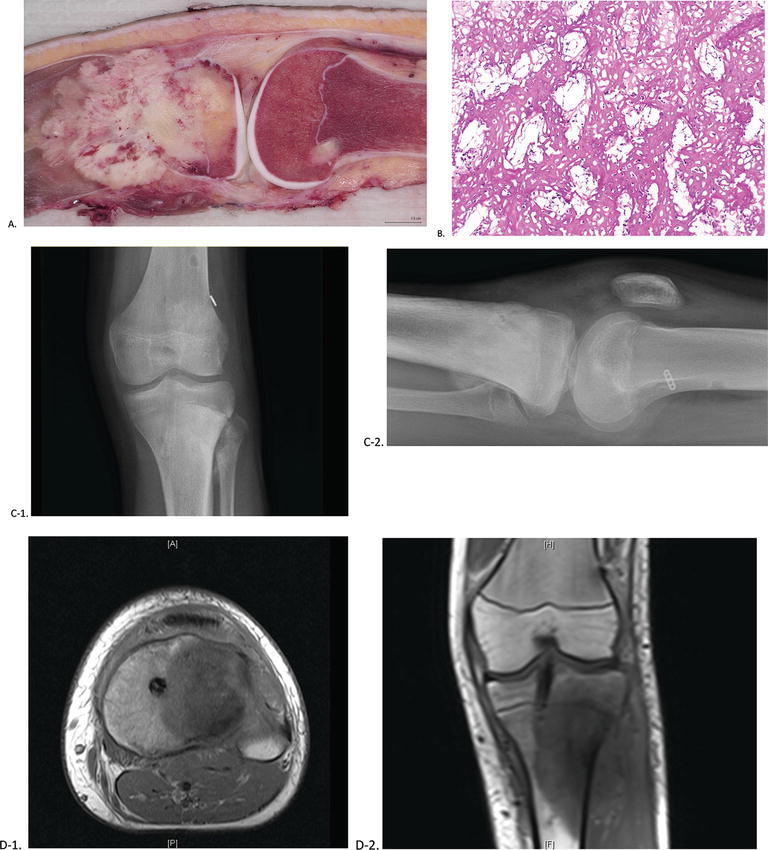

Histological features of canine mammary gland tumours. A, B-simple …